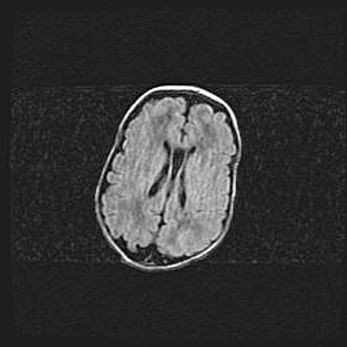

Сообщающаяся гидроцефалия. Кистозная энцефаломаляция головного мозга.

Возраст: 3 месяца 4 дня

Вес: 3100 г

Пол: женский

Окружность головы: 34 см

Срок гестации: 31 неделя

Кистозная энцефаломаляция головного мозга - одна из форм поражения головного мозга в детском возрасте. Характеризуется возникновением множественных и распространённых кист в коре, белом веществе и подкорковых образованиях головного мозга у плодов, новорождённых и детей раннего возраста. Развитие кистозной энцефаломаляции связано с внутриутробной асфиксией и гипотонией, родовой травмой, тромбозом синусов, пороками развития сосудов, инфекциями, сепсисом и другими причинами. Наиболее значимые инфекционные агенты: вирусы простого герпеса, цитомегалии, краснухи, токсоплазмы, энтеробактерии, золотистый стафилококк и другие.